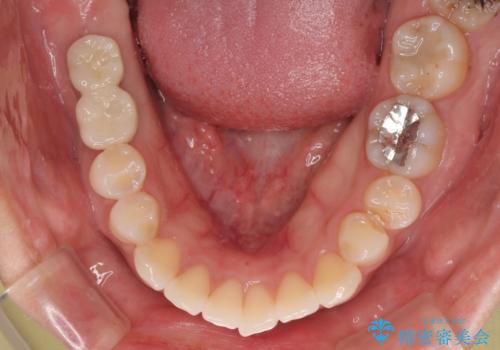

スペースが整った段階で、右下の第一大臼歯と第二大臼歯にインプラントを埋入。

その後、挺出していた右上第一大臼歯と第二大臼歯に装着されていた銀歯についても、審美性と適合性の向上を目的に、オールセラミッククラウンにやり替えました。

これにより、より自然で美しい見た目と、高い精度の咬合が得られています。